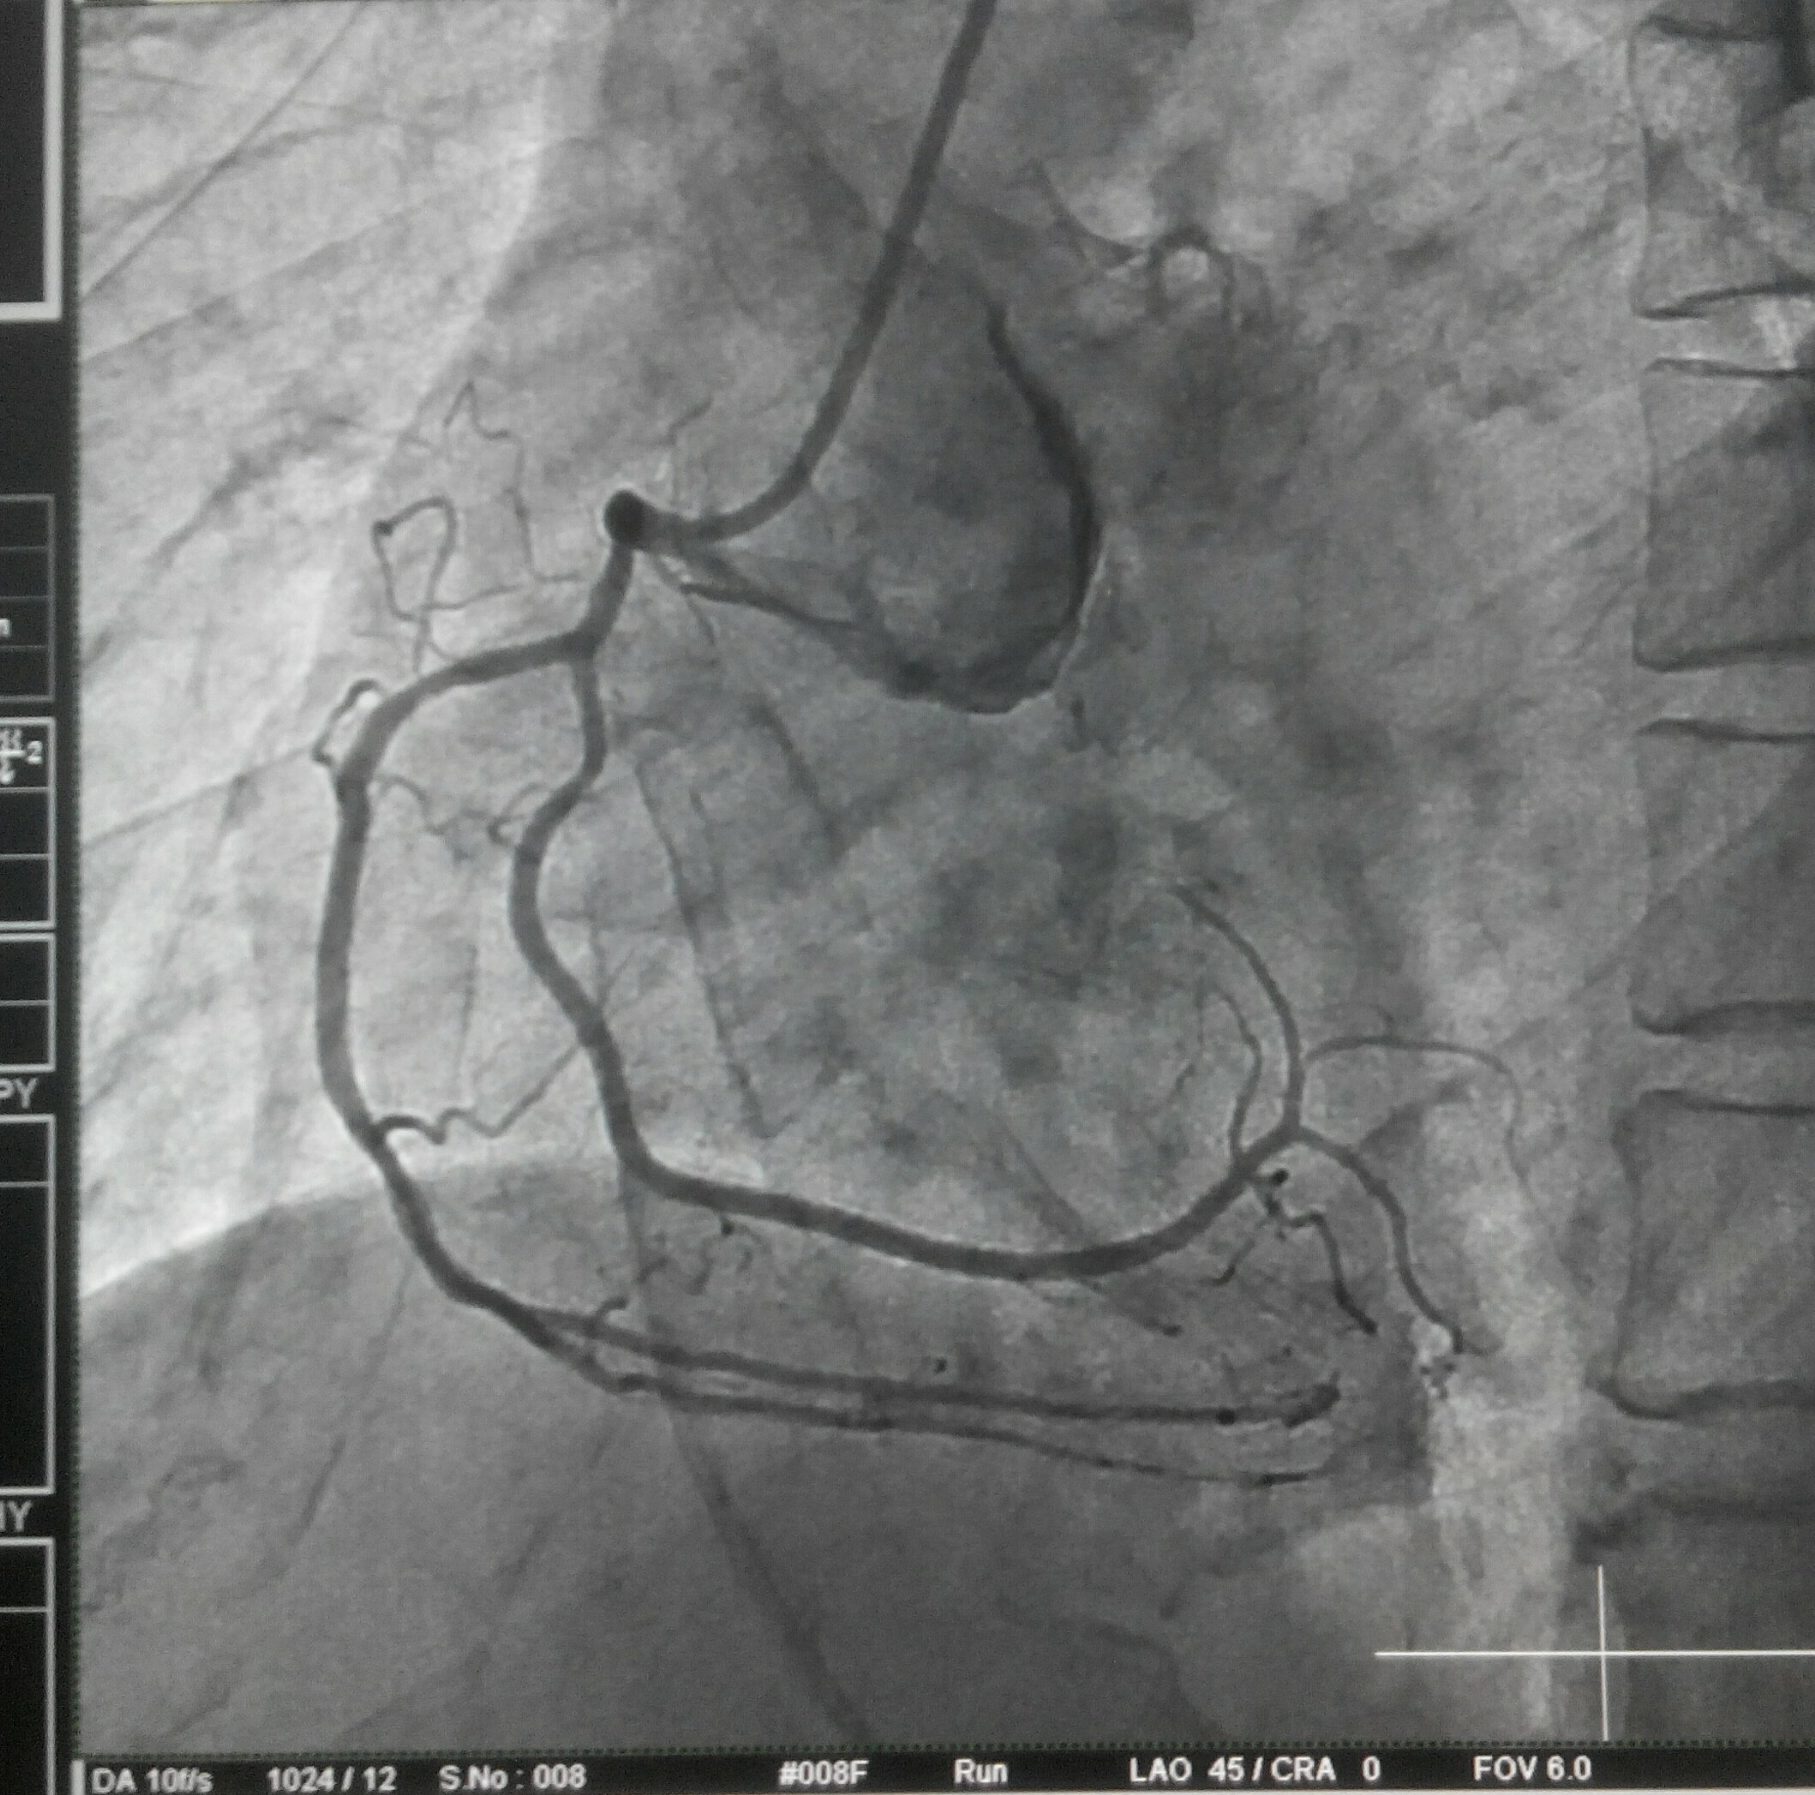

Familiarity with phrenic nerve anatomy is key during an ablation. Specifically, the right phrenic nerve should be carefully delineated during endocardial ablation at key sites, such as SVC, the postero-lateral aspects RA. right superior pulmonary vein, and the junction of the IVC and RA. Fortunately right phrenic nerve never cross over the free wall of RV, unlike the LV,

The left phrenic nerve, on the otherhand, should be localized when performing endocardial ablation near the LAA, ablation of left sided accessory pathways,and epicardial ablation of left ventricular tachycardias